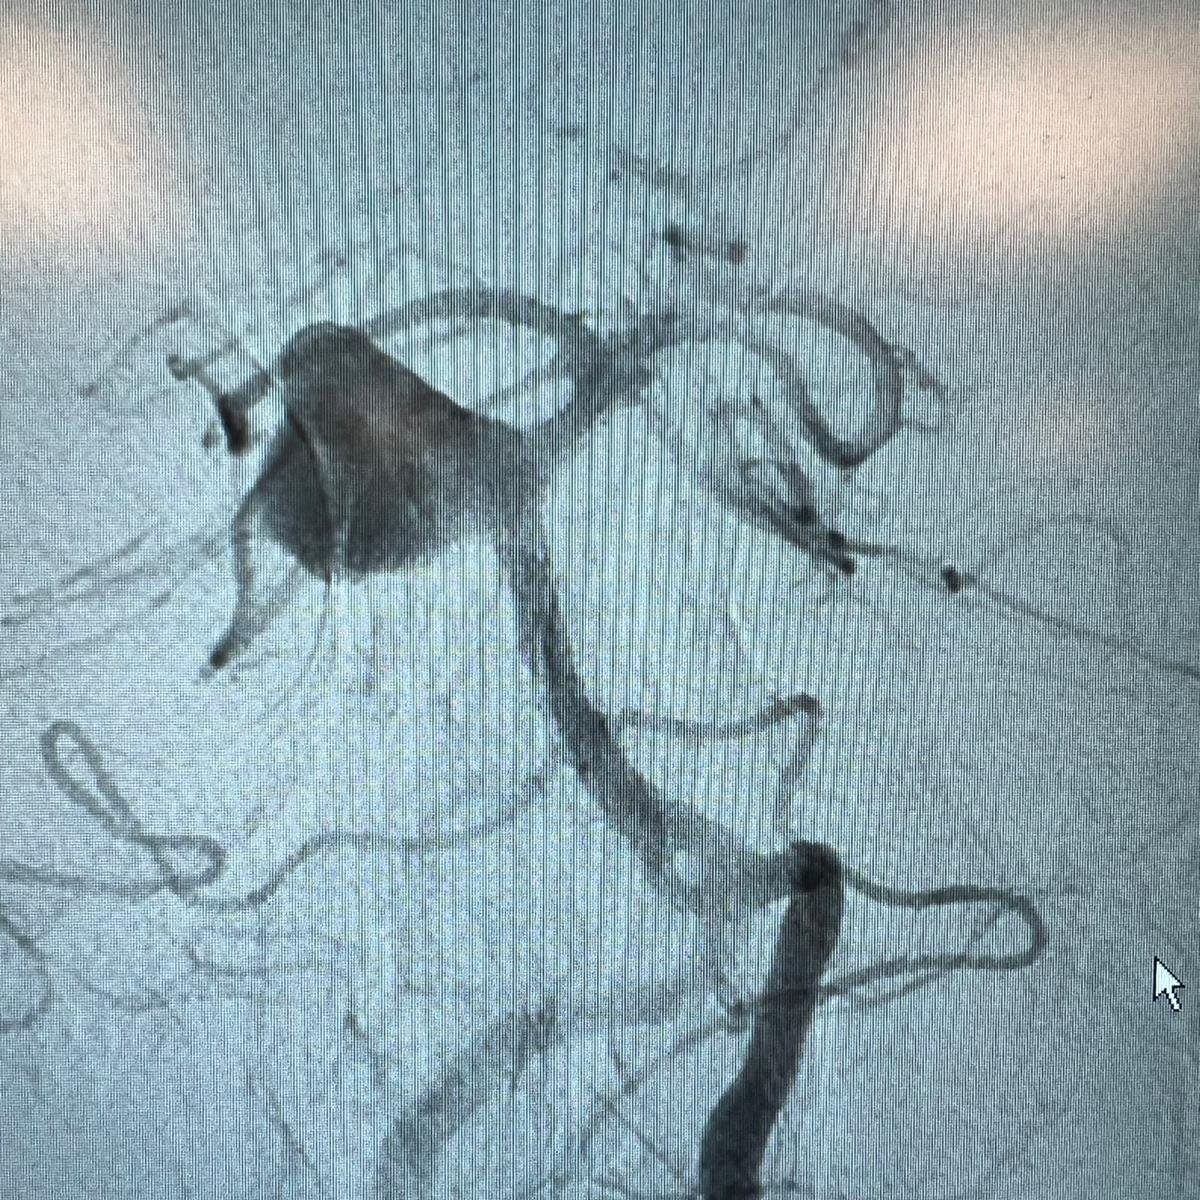

Dr. Shahram Majidi, MD. from Mount Sinai Neurosurgery NY, shares his recent MCA bifurcation aneurysm assisted coiling by #Comaneci17. The #Comaneci, delivered through an SL-10, has been placed in the superior division providing great support and scaffolding for the coils to sit properly.